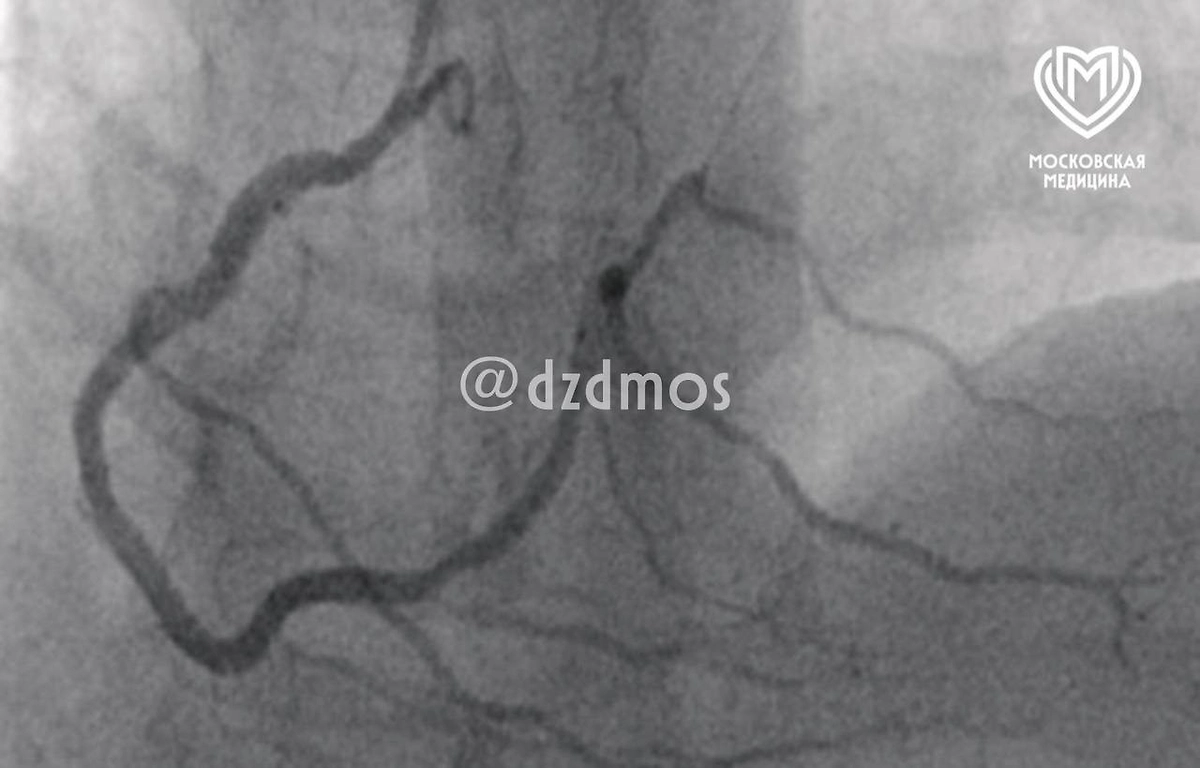

Кусок свинины вызвал у мужчины аллергический инфаркт. Фото © Telegram / Московская медицина

Как пояснила заведующая анестезиолого-реанимационным отделением Мария Наумова, это редкий случай синдрома Коуниса первого типа, когда аллергическая реакция провоцирует острый коронарный синдром.

«Синдром Коуниса — это острый коронарный синдром (например, инфаркт миокарда, спазм коронарных артерий или нестабильная стенокардия), вызванный аллергической реакцией», — рассказала Наумова.